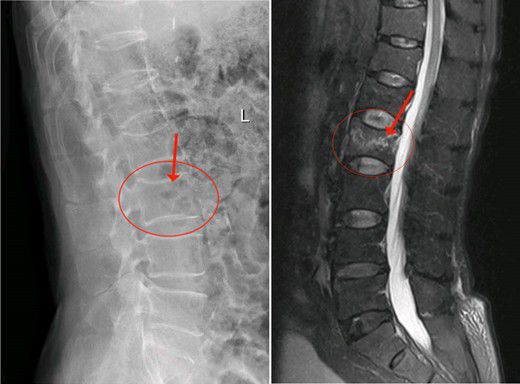

2月3日陳大伯由家人送到我院治療,收入外四科(骨科)。經腰椎MR檢查,發現腰椎第二椎體(L2)壓縮性骨折,椎體中間前緣壓縮變空。高齡患者如果采用保守治療,往往骨折遷延難愈,需要卧床至少1個月以上。老年人基礎疾病多,如陳大伯就患有高血壓、糖尿病、陳舊性心肌梗死等疾病,長期卧床容易誘發各類并發症而危急生命。而傳統開放性手術創傷大,高齡患者難以承受。這也是以往老年人最怕骨折的原因。

△腰椎第二椎體(L2)壓縮性骨折